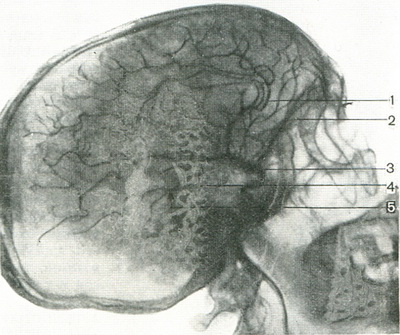

Судини мозку контрастують через загальну сонну артерію, внутрішню сонну (каротидна ангіографія) і хребтову (вертебральная ангіографія) артерії. Негайно після введення контрастної речовини в судини виготовляють знімки у бічній і прямій проекціях. У нормі судини мозку рівномірно заповнюються контрастним речовиною, їх діаметр зменшується, починаючи від судин основи мозку в напрямку до периферії. Судини мають чіткі контури, прямі, без значних вигинів і уривчастості (рис. 397).

397. Артериограмма мозку (по Л. Д. Линденбратену).

1 - передня мозкова артерія; 2 - очна артерія; 3 - внутрішня сонна артерія; 4 - середня мозкова артерія; 5 - артерія судинного сплетення.